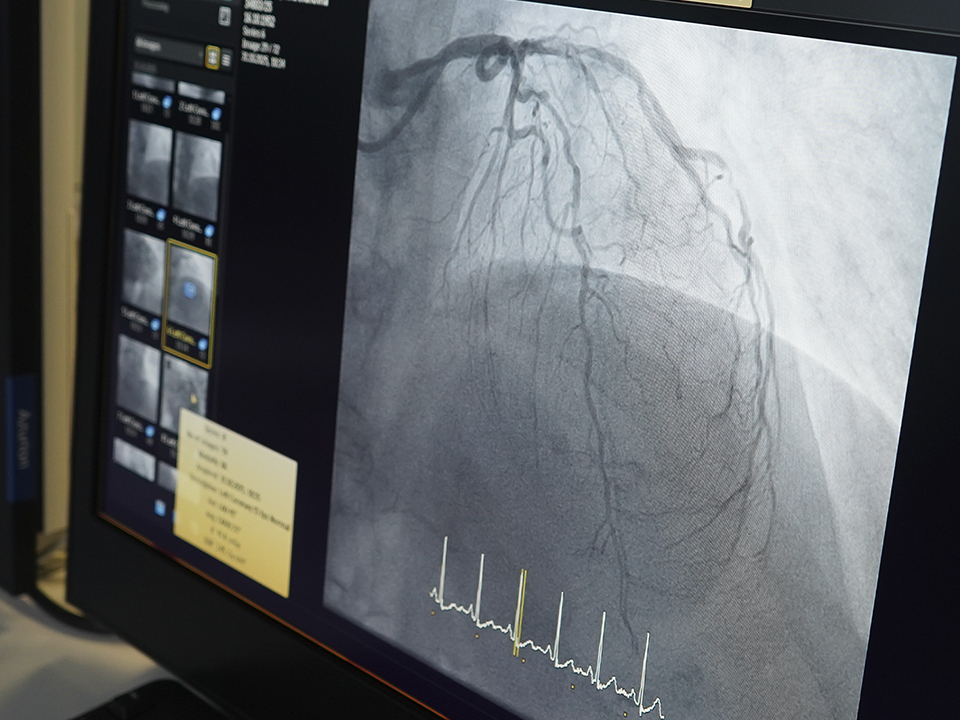

В конце октября Анна Аношина при поддержке наставника успешно выполнила операцию по стентированию коронарной артерии. Пациентку доставили с болями в сердце и диагнозом «стенокардия». Врачи провели коронарографию, выявили критическое сужение и имплантировали стент через небольшой прокол на руке.